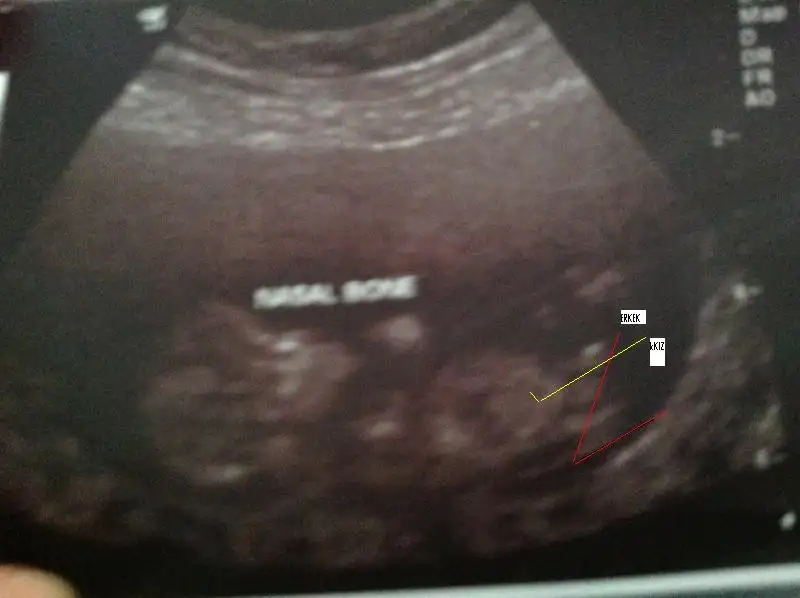

Bebişimin 13 haftalık önden çekilmiş resmi bacak arasındaki nub belli oluyor sizin için işaretledim

Sizce bebişim oğlanmı kızmı :) Yorumlarınız için şimdiden teşekkür ediyorum :16:

SENIN ICIN RESIM EKLEDIM CIZDIM CNM seninkinin ucu yukarda

senin resimle yandaki resimdeki fark yandaki resim kiz paralel